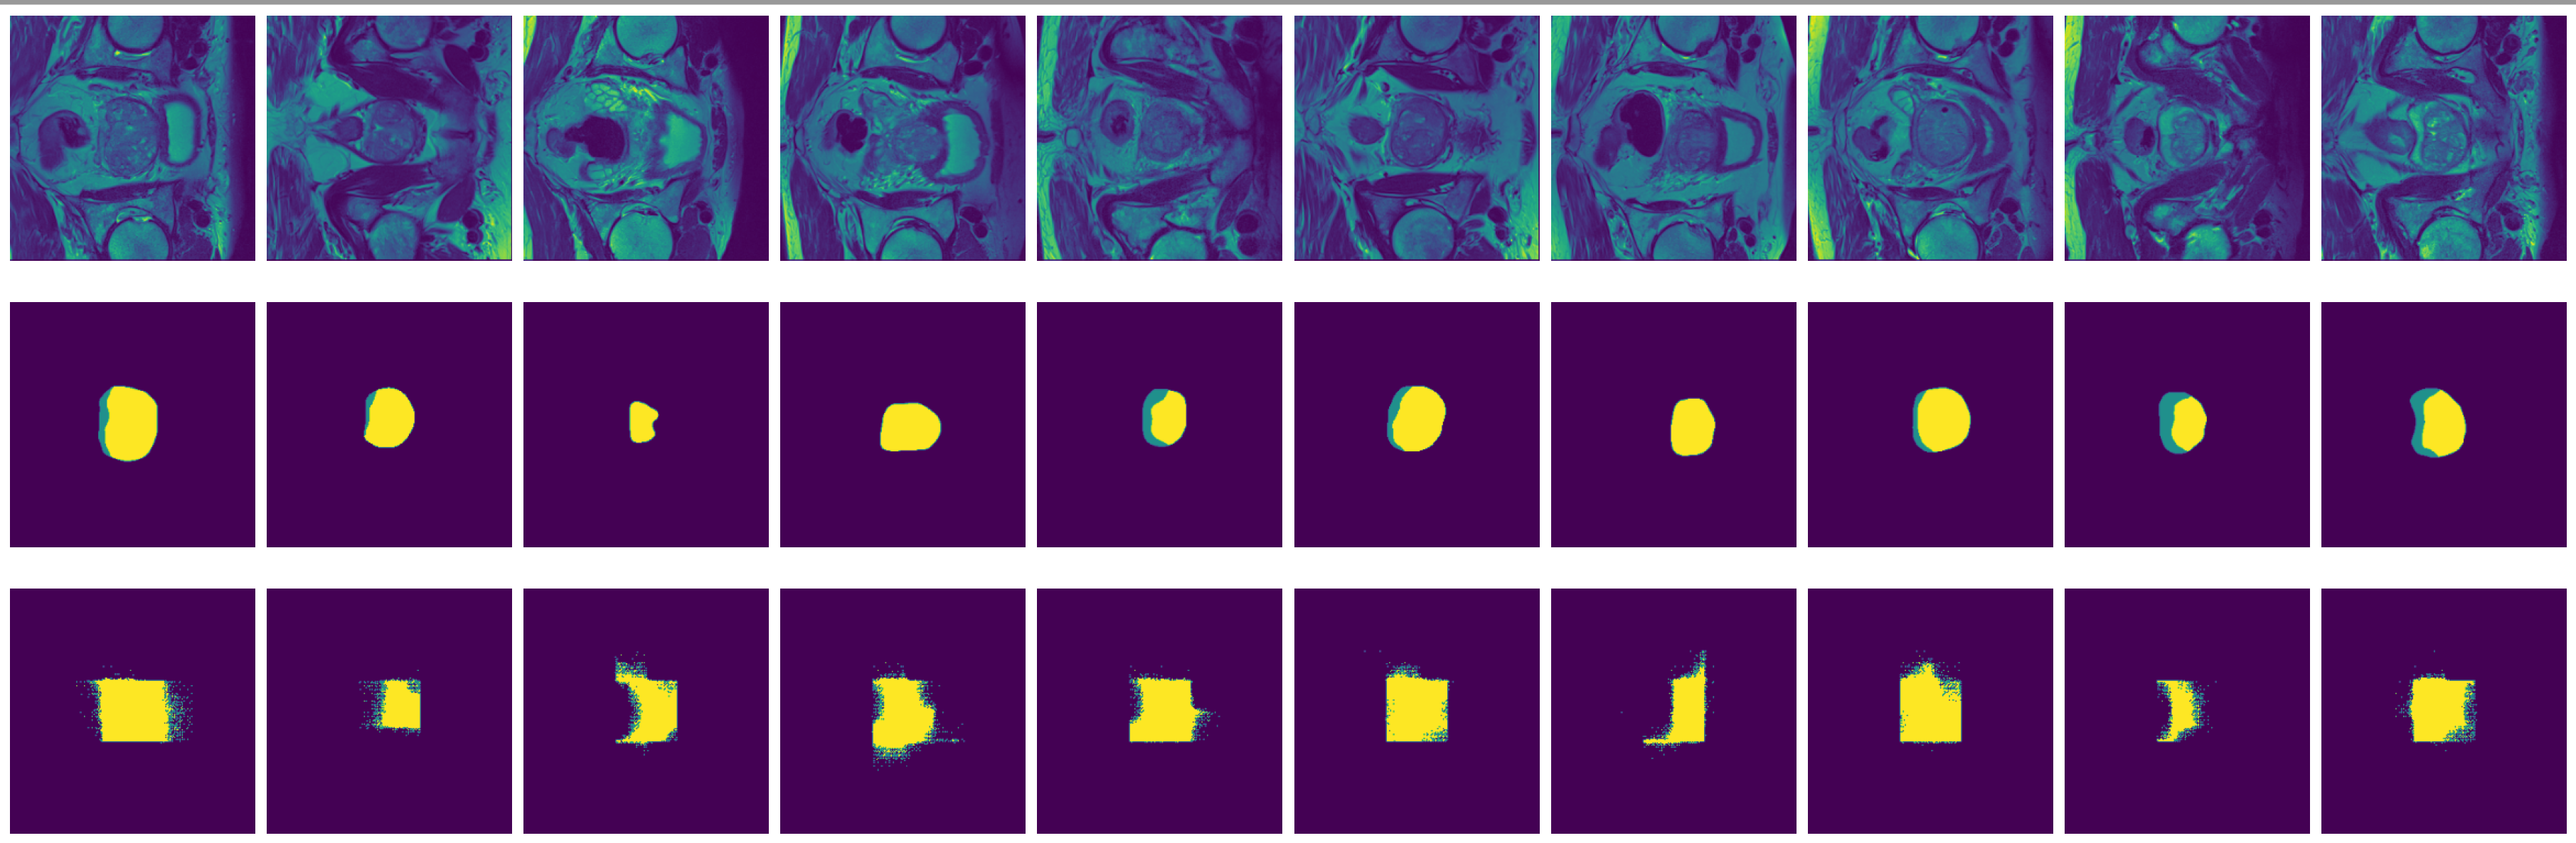

Figure 8: True (top) and predicted (bottom) segmentation from FCN trained with data augmented by flipping and rotation.

-

Figure 9: True (top) and predicted (bottom) segmentation from dilated FCN trained with data augmented by flipping and rotation.

FCN is outperformed by the two encoder-decoder models due to the thin deconvolutional layer as decoder and coarse output in the final deconvolutional layer. The dilated FCN managed to improve performance of FCN but is still outperformed by the encoder-decoder models. For the two encoder-decoder based models, U-Net outperforms DeConvNet in general. This is not surprising since U-Net is specifically designed for medical images and is supposed to achieve higher segmentation accuracy with fewer data. Moreover, randomly flipping input images seems to help improve performance for both of the models. Figure 8 and Figure 9 are the true (top) and predicted (bottom) segmentation of 10 test images from FCN and dilated FCN trained with data augmented by flipping and rotation. Figure 10 and Figure 11 are the true (top) and predicted (bottom) segmentation of 10 test images from DeConvNet and U-Net trained with data augmented by flipping and rotation. It can be seen that U-Net gives a smoother edge than FCN, dilated FCN and DeConvNet.